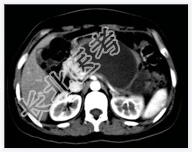

- [材料题] 患者,女性,31岁,反复上腹部疼痛1年,加重1天入院。B超示胰腺体尾部囊性病变,性质待定。行上腹部CT增强扫描。

- 简答题1、请问该患者诊断是什么?

- 简答题2、诊断依据是什么?

- 简答题3、鉴别诊断有哪些?